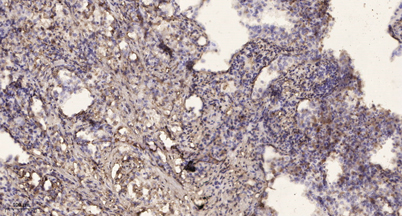

Product name: Islet-2 rabbit pAb

Dilutions: WB 1:500-2000;IHC-p 1:50-300

Immunogen: The antiserum was produced against synthesized peptide derived from human ISL2. AA range:161-210